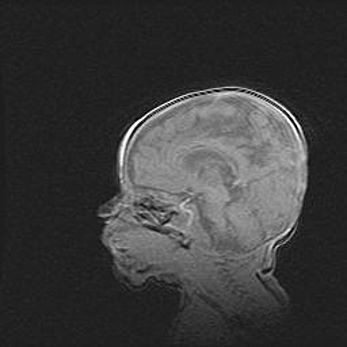

Церебральная ишемия II.

Возраст: 5 дней

Вес: 3400 г

Пол: женский

Окружность головы: 35 см

Срок гестации: 39 недель

Церебральная ишемия – это заболевание, характеризующееся недостаточностью (гипоксией) либо полным прекращением (аноксией) снабжения мозга кислородом по причине закупорки одного или нескольких сосудов. Это приводит к  что метаболическим расстройствам различной степени тяжести в тканях головного мозга, развитию коагуляционных некрозов и гибели нейронов.